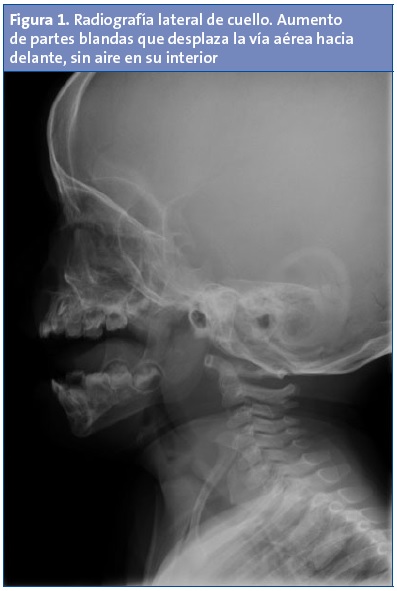

Pruebas complementarias iniciales: hemograma con leucocitosis (27 370/mm3) y neutrofilia, trombocitosis (510 000/mm3); el resto de los parámetros hemáticos se encontraban en rangos normales. Proteína C reactiva en 7,5 mg/dl. Cultivos de sangre, orina y líquido cefalorraquídeo negativos. Cultivo del contenido purulento del absceso: Streptococcus mitis y Streptococcus oralis. Radiografía lateral del cavum: aumento de partes blandas que desplaza la vía aérea hacia delante, sin aire en su interior (Fig. 1). Ecografía: múltiples adenopatías laterocervicales bilaterales y acúmulo de material heterogéneo en espacio retrofaríngeo compatible con absceso.